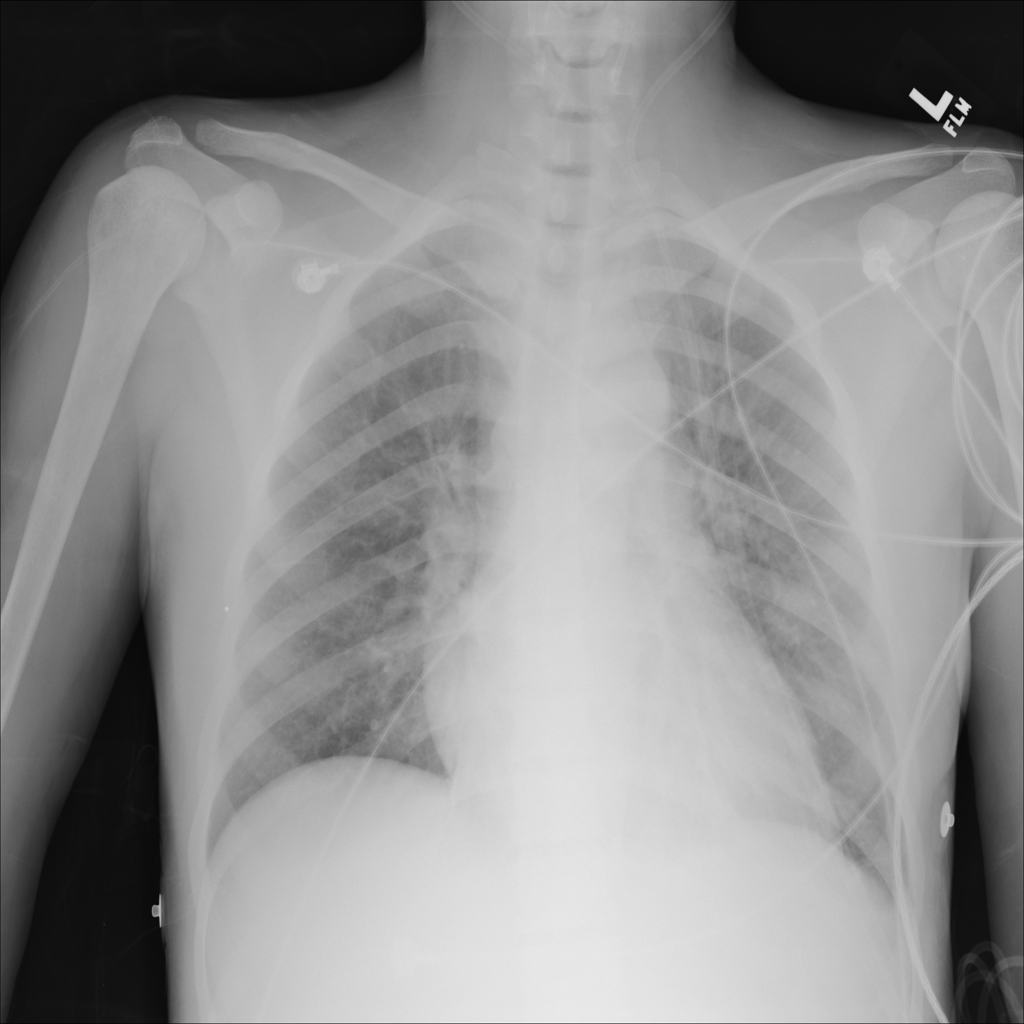

Cardiomegaly

Cardiomegaly means the heart appears enlarged on the chest X-ray. It is a descriptive imaging finding that can be related to heart strain, chronic pressure or volume changes, or even projection effects.

Showing up to 90 reference images for Cardiomegaly.

PAT-4639 · IMG-045Cardiomegaly

PAT-4639 · IMG-045

PA